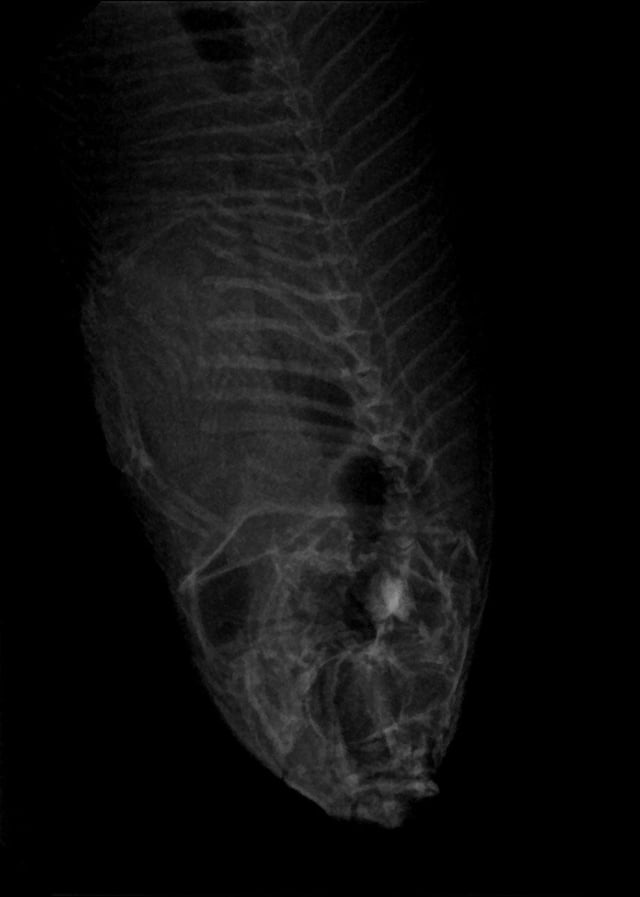

This is what happens when you work at a vet clinic and have a clinic betta…

Oh and we ended up having to take his photos with the dental x-ray. The table was just too big to get clarity